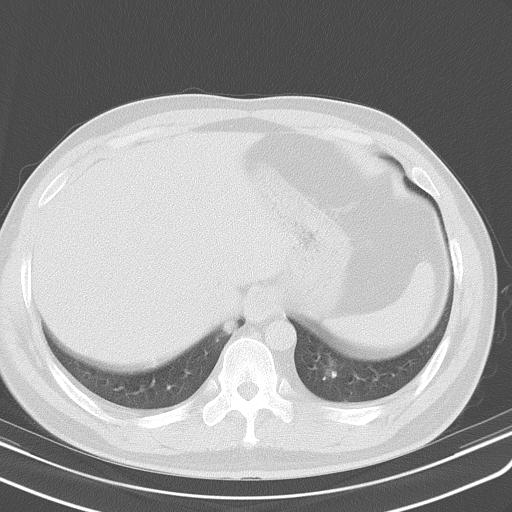

患者男性 35 主因发热咳嗽四天,血象不高,心肺听诊未见异常,无其它病史及传染病接触史。

一周后复查胸片基本正常

补充一下各种检查结果,病人无痰,胸闷,ppd及结核抗体阴性,wbc7.5x10的9次方,血沉22mm/h,crp及抗链o阳性。

经一周抗炎抗病毒治疗复查胸片示病变大部吸收,基本恢复正常,未做气管镜检查,考虑为炎性变或霉菌感染。